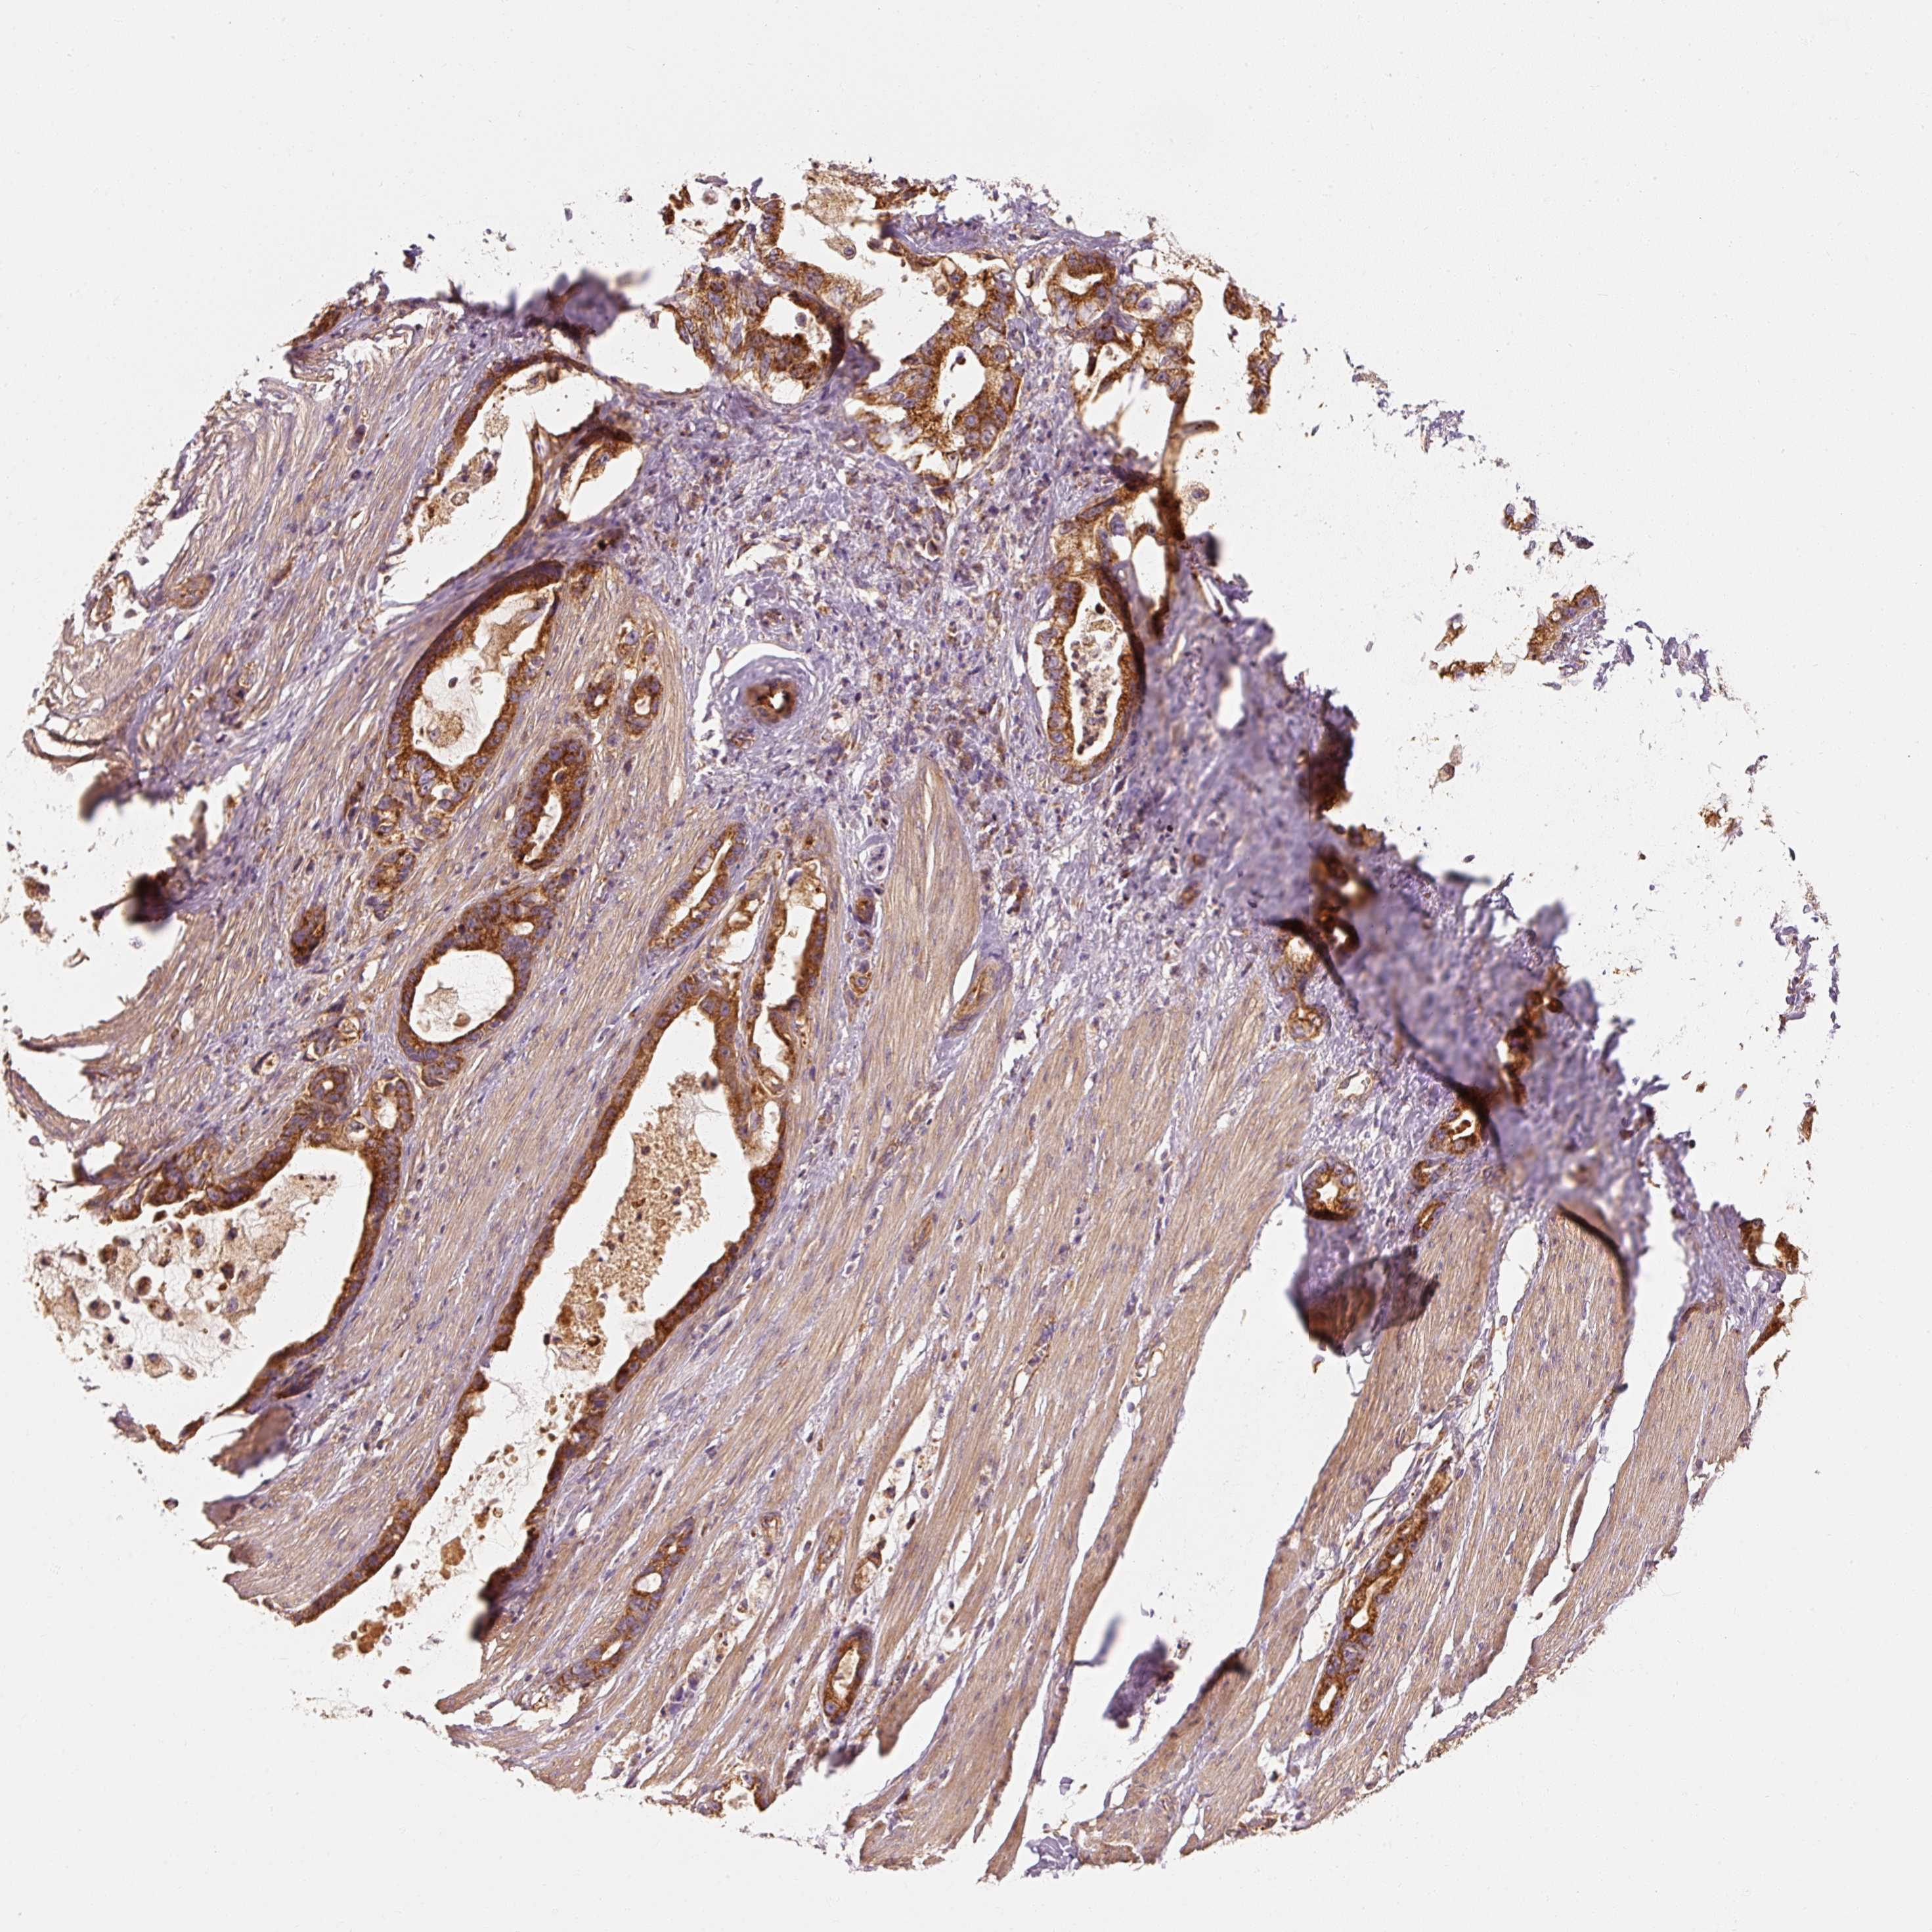

STOMACH CANCER - Protein expressioni

A mouse-over function shows sample information and annotation data. Click on an image to view it in a full screen mode. Samples can be filtered based on level of antibody staining by selecting one or several of the following categories: high, medium, low and not detected. The assay and annotation is described here.

Note that samples used for immunohistochemistry by the Human Protein Atlas do not correspond to samples in the TCGA dataset.

Antibody stainingi

Antibody staining in the annotated cell types in the current human tissue is reported as not detected, low, medium, or high, based on conventional immunohistochemistry profiling in selected tissues. This score is based on the combination of the staining intensity and fraction of stained cells.

Each image is clickable and will lead to virtual microscopy that enables deeper exploration of all samples and also displays staining intensity scores, fraction scores and subcellular localization as well as patient and tissue information for each sample.

Antibody HPA036231

Antibody HPA036232

Staining

High

Medium

Low

Not detected

Intensity

Strong

Moderate

Weak

Negative

Quantity

>75%

75%-25%

<25%

None

Location

Nuclear

Cytoplasmic/membranous

Cytoplasmic/membranous,nuclear

Adenocarcinoma, NOS